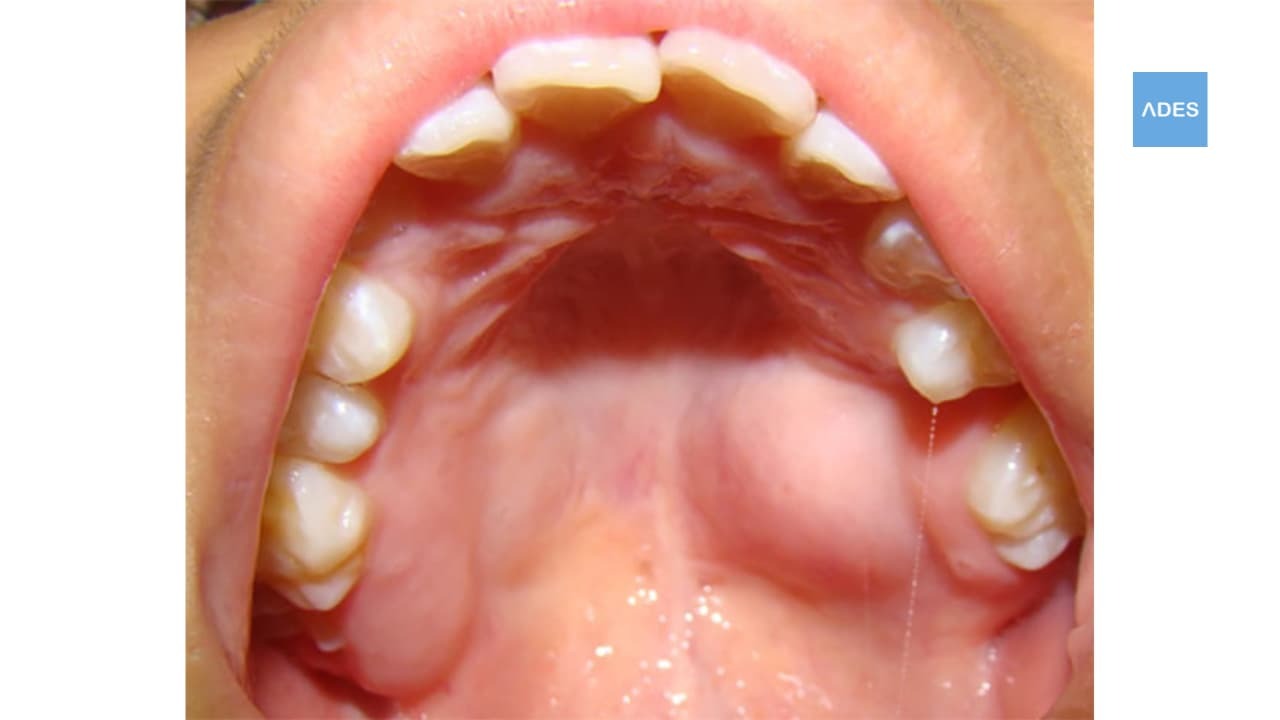

¿Has notado que tu paladar está inflamado o te duele al comer? Aunque muchas veces es un problema leve, en algunos casos puede indicar una infección o enfermedad bucal que necesita atención profesional. En Clínica Dental ADES, en Badajoz, te ayudamos a identificar la causa y a tratar el problema con las mejores soluciones.

El paladar inflamado puede tener varias causas, desde irritaciones leves hasta infecciones más serias. Algunas de las más comunes incluyen:

¿Cuándo Deberías Preocuparte por un Paladar Inflamado?

⚠️ Si la inflamación dura más de 10 días.

⚠️ Si tienes fiebre o ganglios inflamados.

⚠️ Si aparecen llagas o heridas que no cicatrizan.

⚠️ Si sientes dolor intenso al comer o beber.